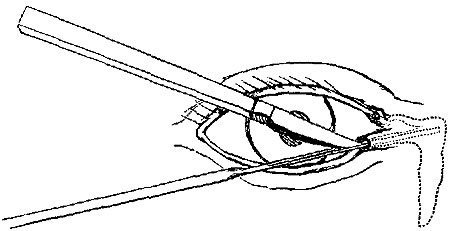

OPERATIONS ON THE EYE AND ITS APPENDAGES. | |

| Entropium and Ectropium—Trichiasis—Tarsal Tumours—On Lachrymal Organs—Mr. Bowman's Operation—Pterygium—Strabismus, convergent and divergent—Paracentesis of the Anterior Chamber—Operations for Cataract by Displacement, Solution, and Extraction—Various methods of Extraction—Operations for Artificial Pupil—Iridesis—Corelysis—Iridectomy—Excision of Staphyloma—Excision of Eyeball, | 151-174 |